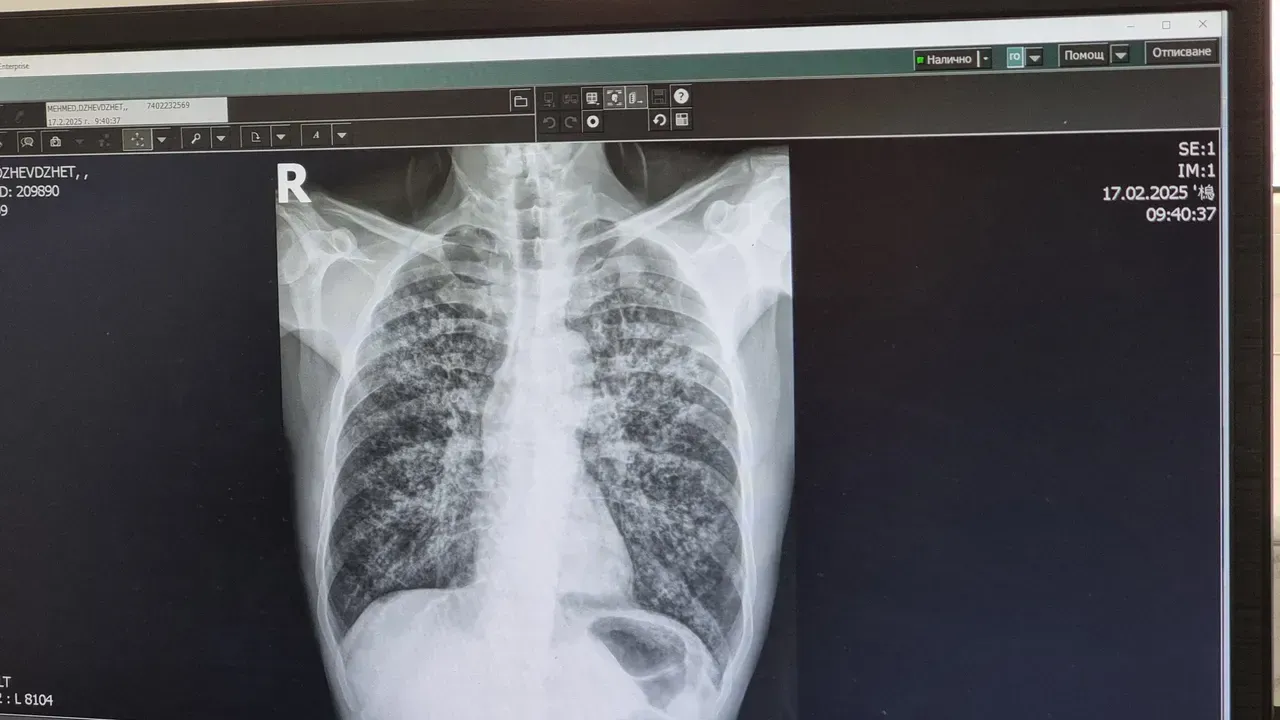

Безплатни прегледи за туберкулоза в Пловдив

Кампанията на УМБАЛ „Свети Георги“ цели ранно откриване и превенция на заболяването

Кампанията предлага скрининг и консултации от 19 до 31 март по повод Световния ден за борба със заболяването